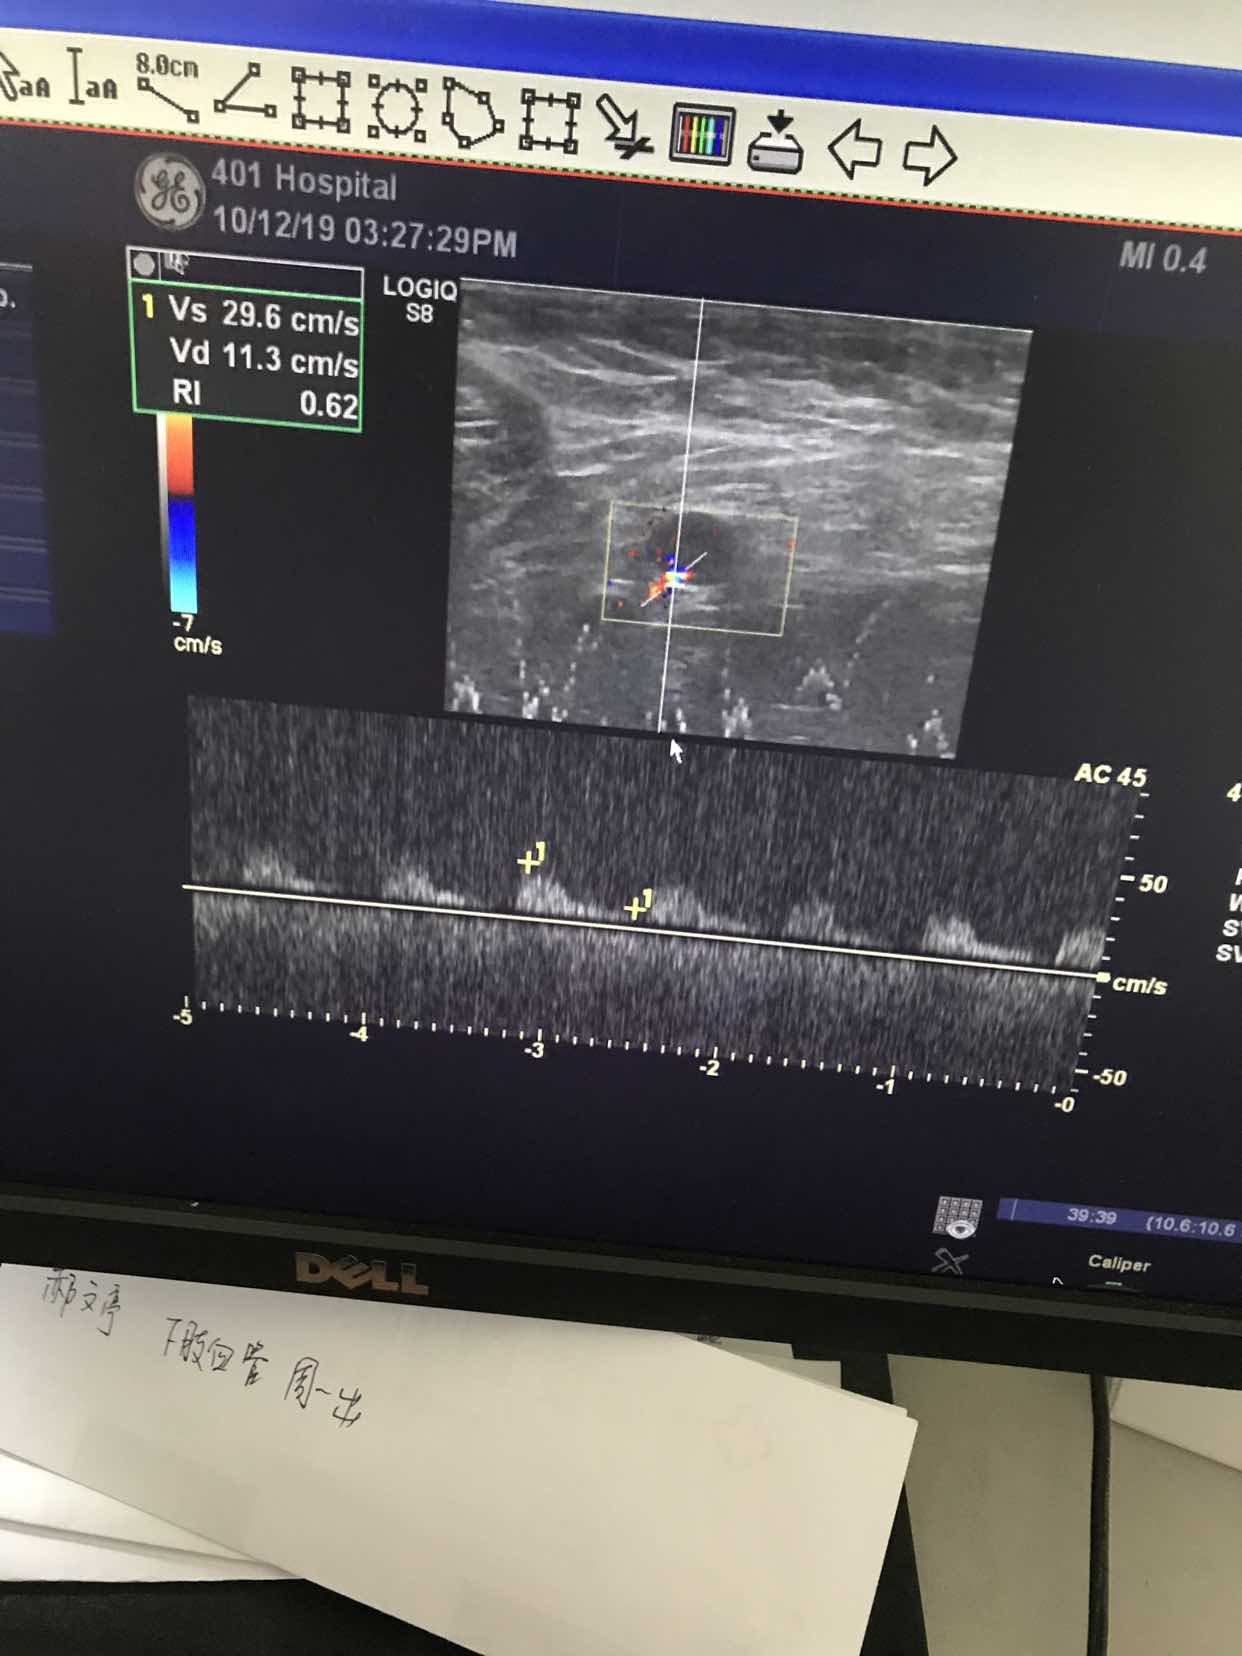

是淋巴吗?多大啊?报告怎么说的